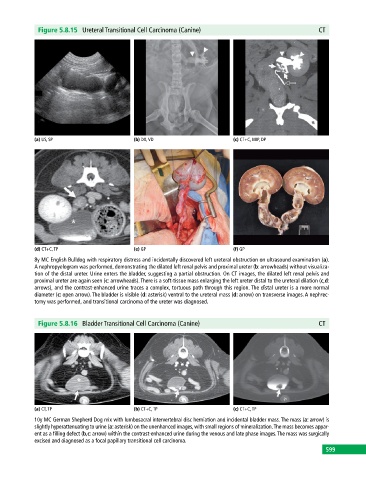

Figure 5.8.15 Ureteral Transitional Cell Carcinoma (Canine) CT

(a) US, SP (b) DX, VD (c) CT+C, MIP, DP

(d) CT+C, TP (e) GP (f) GP

8y MC English Bulldog with respiratory distress and incidentally discovered left ureteral obstruction on ultrasound examination (a).

A nephropyelogram was performed, demonstrating the dilated left renal pelvis and proximal ureter (b: arrowheads) without visualiza-

tion of the distal ureter. Urine enters the bladder, suggesting a partial obstruction. On CT images, the dilated left renal pelvis and

proximal ureter are again seen (c: arrowheads). There is a soft‐tissue mass enlarging the left ureter distal to the ureteral dilation (c,d:

arrows), and the contrast‐enhanced urine traces a complex, tortuous path through this region. The distal ureter is a more normal

diameter (c: open arrow). The bladder is visible (d: asterisk) ventral to the ureteral mass (d: arrow) on transverse images. A nephrec-

tomy was performed, and transitional carcinoma of the ureter was diagnosed.

Figure 5.8.16 Bladder Transitional Cell Carcinoma (Canine) CT

(a) CT, TP (b) CT+C, TP (c) CT+C, TP

10y MC German Shepherd Dog mix with lumbosacral intervertebral disc herniation and incidental bladder mass. The mass (a: arrow) is

slightly hyperattenuating to urine (a: asterisk) on the unenhanced images, with small regions of mineralization. The mass becomes appar-

ent as a filling defect (b,c: arrow) within the contrast‐enhanced urine during the venous and late phase images. The mass was surgically

excised and diagnosed as a focal papillary transitional cell carcinoma.